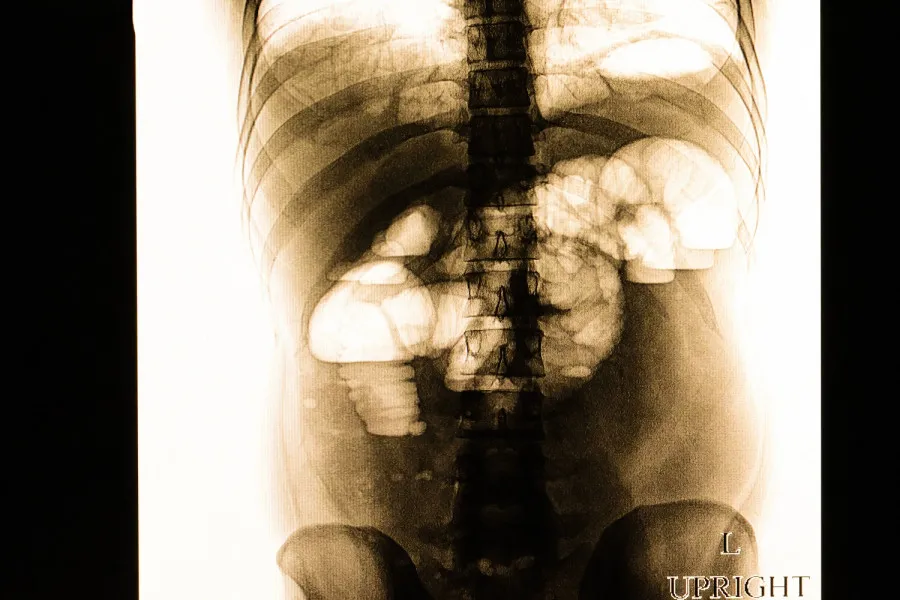

Στις 17 Απριλίου 2026, η Μαρέβα Γκραμπόφσκι – Μητσοτάκη εισήχθη στο Νοσοκομείο ΓΝΑ “Ο ΕΥΑΓΓΕΛΙΣΜΟΣ” με έντονο κοιλιακό άλγος. Η διάγνωση ήταν αποφρακτικός ειλεός, μια κατάσταση που μπορεί να οδηγήσει σε σοβαρές επιπλοκές.

Αμέσως, οι γιατροί προχώρησαν σε λαπαροτομία, μια χειρουργική διαδικασία που αποδείχθηκε επιτυχής. Ο ειλεός μπορεί να προκληθεί από φυσικά εμπόδια ή μειωμένη κινητικότητα του εντέρου — και η κατάσταση αυτή απαιτεί άμεση παρέμβαση.

Η Μαρέβα υπέστη αυτή την κρίσιμη κατάσταση λόγω συμφύσεων, κάτι που συμβαίνει συχνά σε ενήλικες. Στους ενήλικες, οι πιο κοινές αιτίες περιλαμβάνουν κήλες και ενδοκοιλιακές συμφύσεις.

Η σημασία αυτής της εξέλιξης είναι μεγάλη, δεδομένου ότι ο ειλεός μπορεί να προκαλέσει ισχαιμία ή ακόμη και διάτρηση του εντέρου, γεγονός που θέτει σε κίνδυνο τη ζωή του ασθενούς.